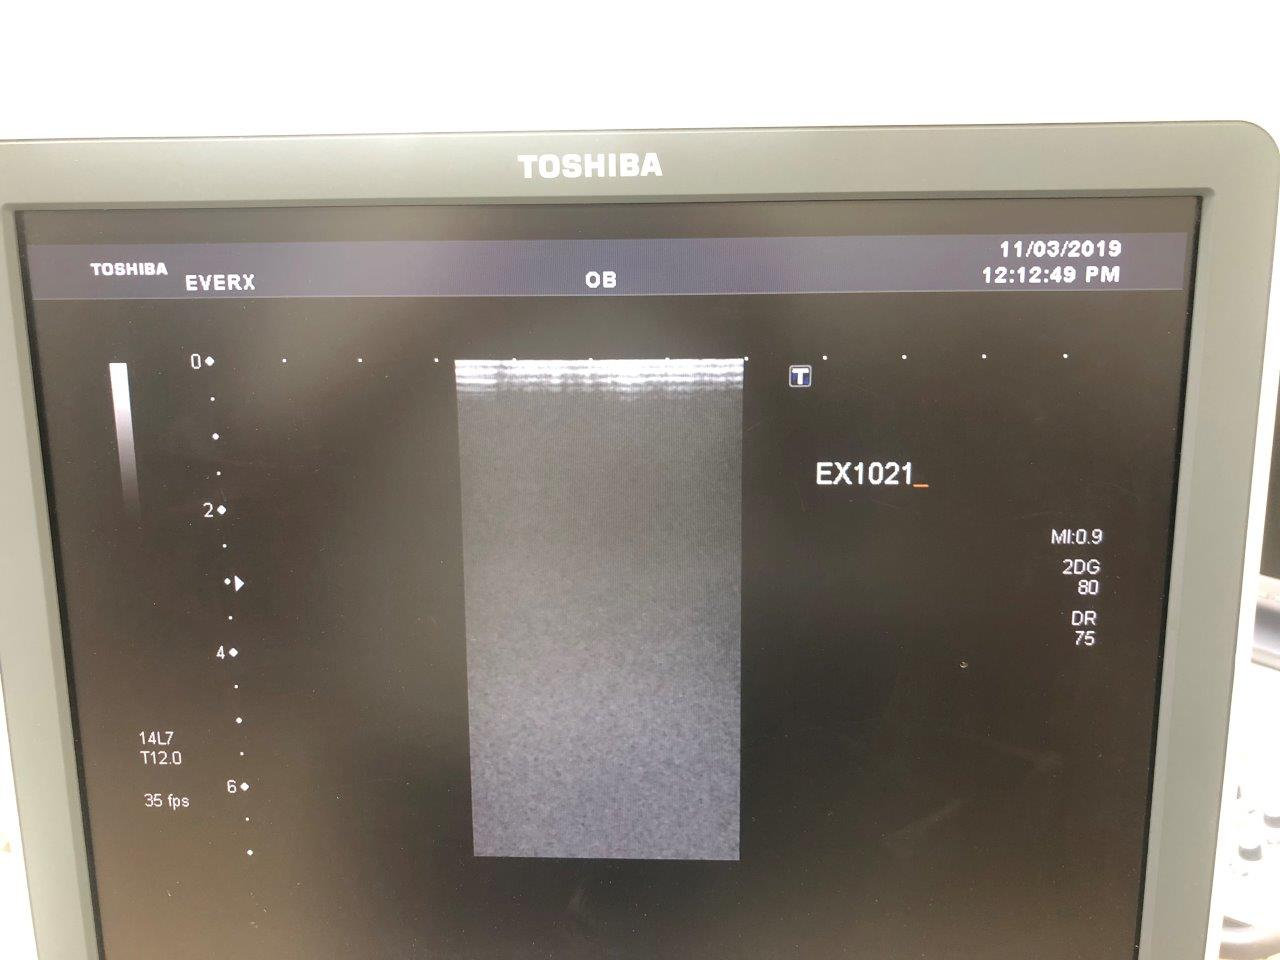

Used Toshiba Xario XG – good condition

Our Ref no. EX1020,

Multiple Probes to choose from: PVT 375BT, PVT 661VT, PLT 1204AT, PLT 704SBT